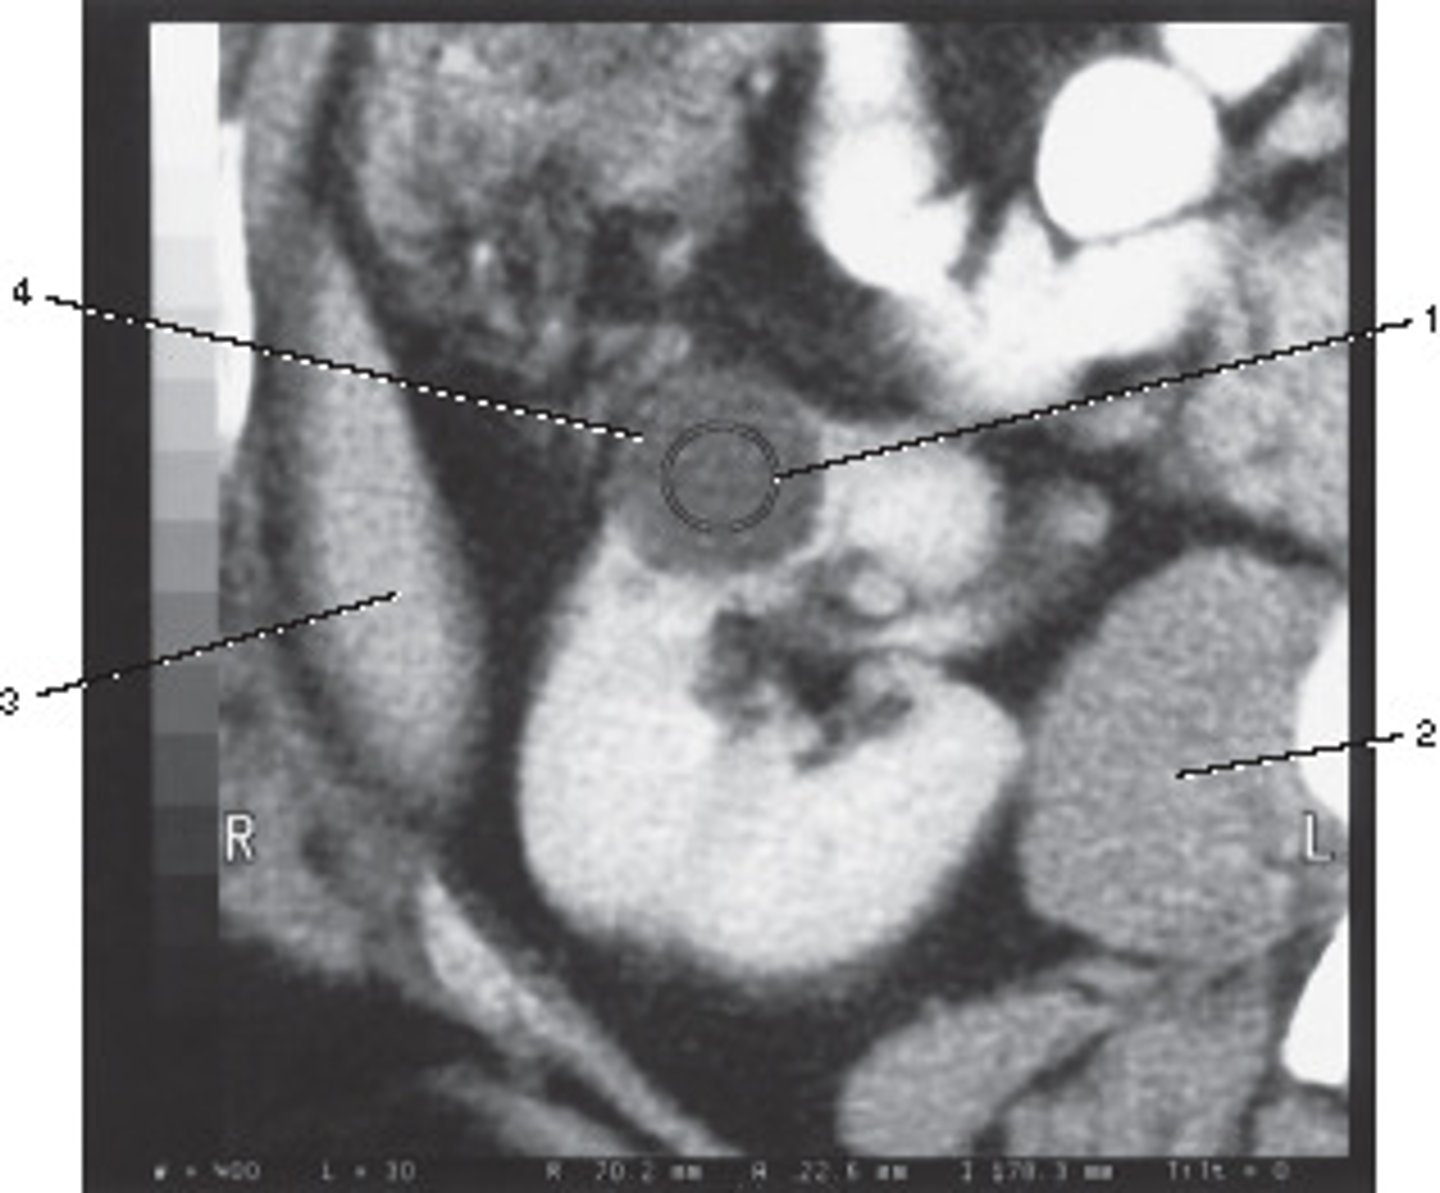

Corticomedullary;

30-40 seconds after injection,

the corticomedullary phase demonstrates optimal enhancement of the renal cortex with maximum differentiation from the renal medulla

This image of the abdomen was most likely acquired in which in which renal enhancement phase?

<p>This image of the abdomen was most likely acquired in which in which renal enhancement phase?</p>

Renal Cortex

Number 1 corresponds to which of the following?

<p>Number 1 corresponds to which of the following?</p>